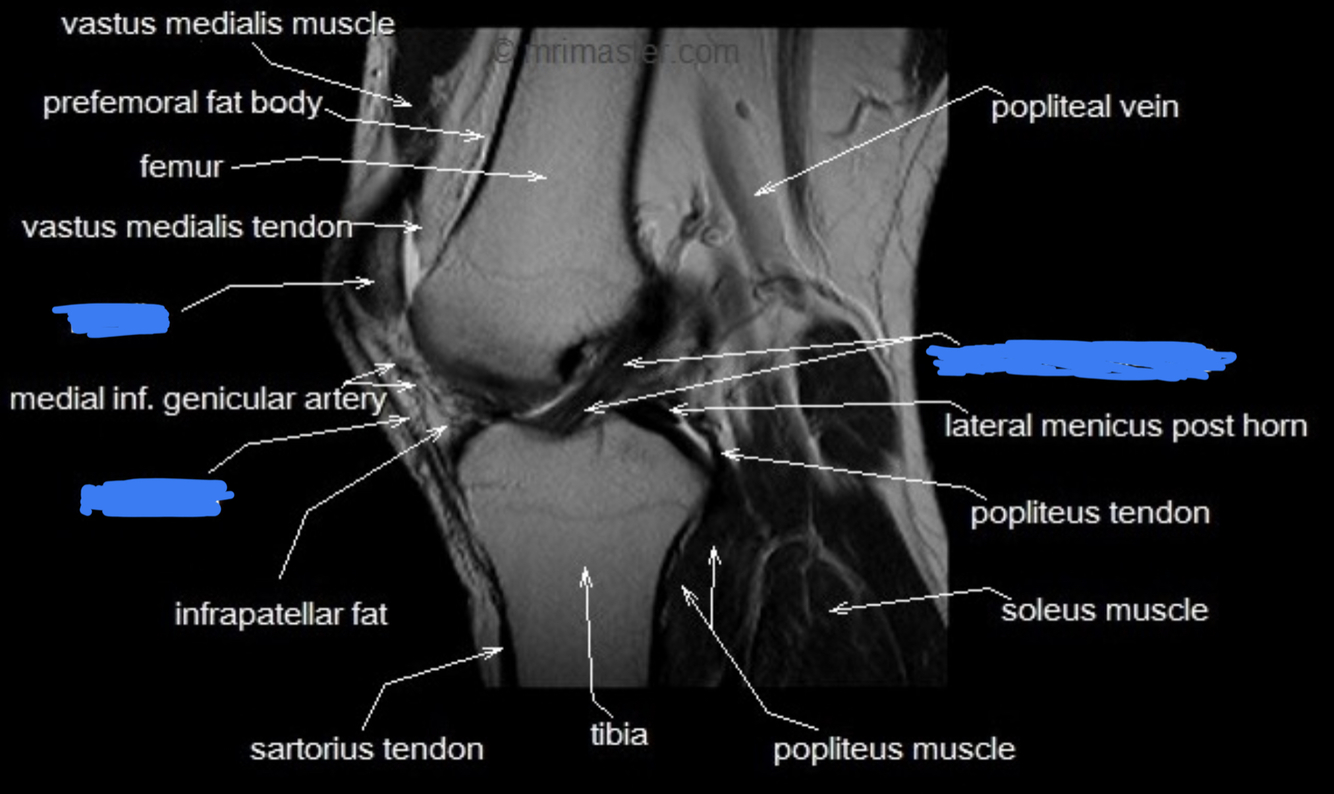

What is this image? Label

T1 weighted MRI of knee, sagittal view